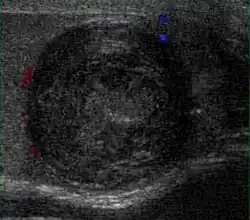

Fibrous pseudotumors, also known as fibromas are thought to be reactive, nonneoplastic lesions. They can occur at any age, about 50% of fibromas are associated with hydrocele, and 30% are associated with a history of trauma or inflammation (Akbar et al., 2003). Although the exact cause of this tumor is not completely understood, it is generally believed that these lesions represent a benign reactive proliferation of inflammatory and fibrous tissue, in response to chronic irritation. Sonographic evaluation generally shows one or more solid nodules arising from the tunica vaginalis, epididymis, spermatic cord and tunica albuginea [Fig. 18]. A hydrocele is frequently present too. The nodules may appear hypoechoic or hyperechoic, depending on the amount of collagen or fibroblast present. Acoustic shadowing may occur in the absence of calcification due to the dense collagen component of this tumor. With color Doppler sonography, a small to moderate amount of vascularity may be seen [Fig. 19].

-

Fig. 18. Fibrous pseudotumor. A homogeneous hypoechoic nodular lesion is seen attached to the tunica associated with minimal amount of hydrocele. -

Fig. 19. Fibrous pseudotumor. With color Doppler, a little vascular flow is seen in this fibrous pseudotumor.